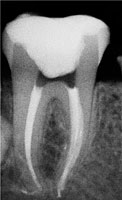

Примеры хорошо запломбированных каналов:

При лечении в одно посещение, зуб сразу восстанавливают пломбой. При лечении в два-три посещения полость зуба сначала закрывается временной пломбой, а в последнее посещение временную пломбу заменяют на постоянную.